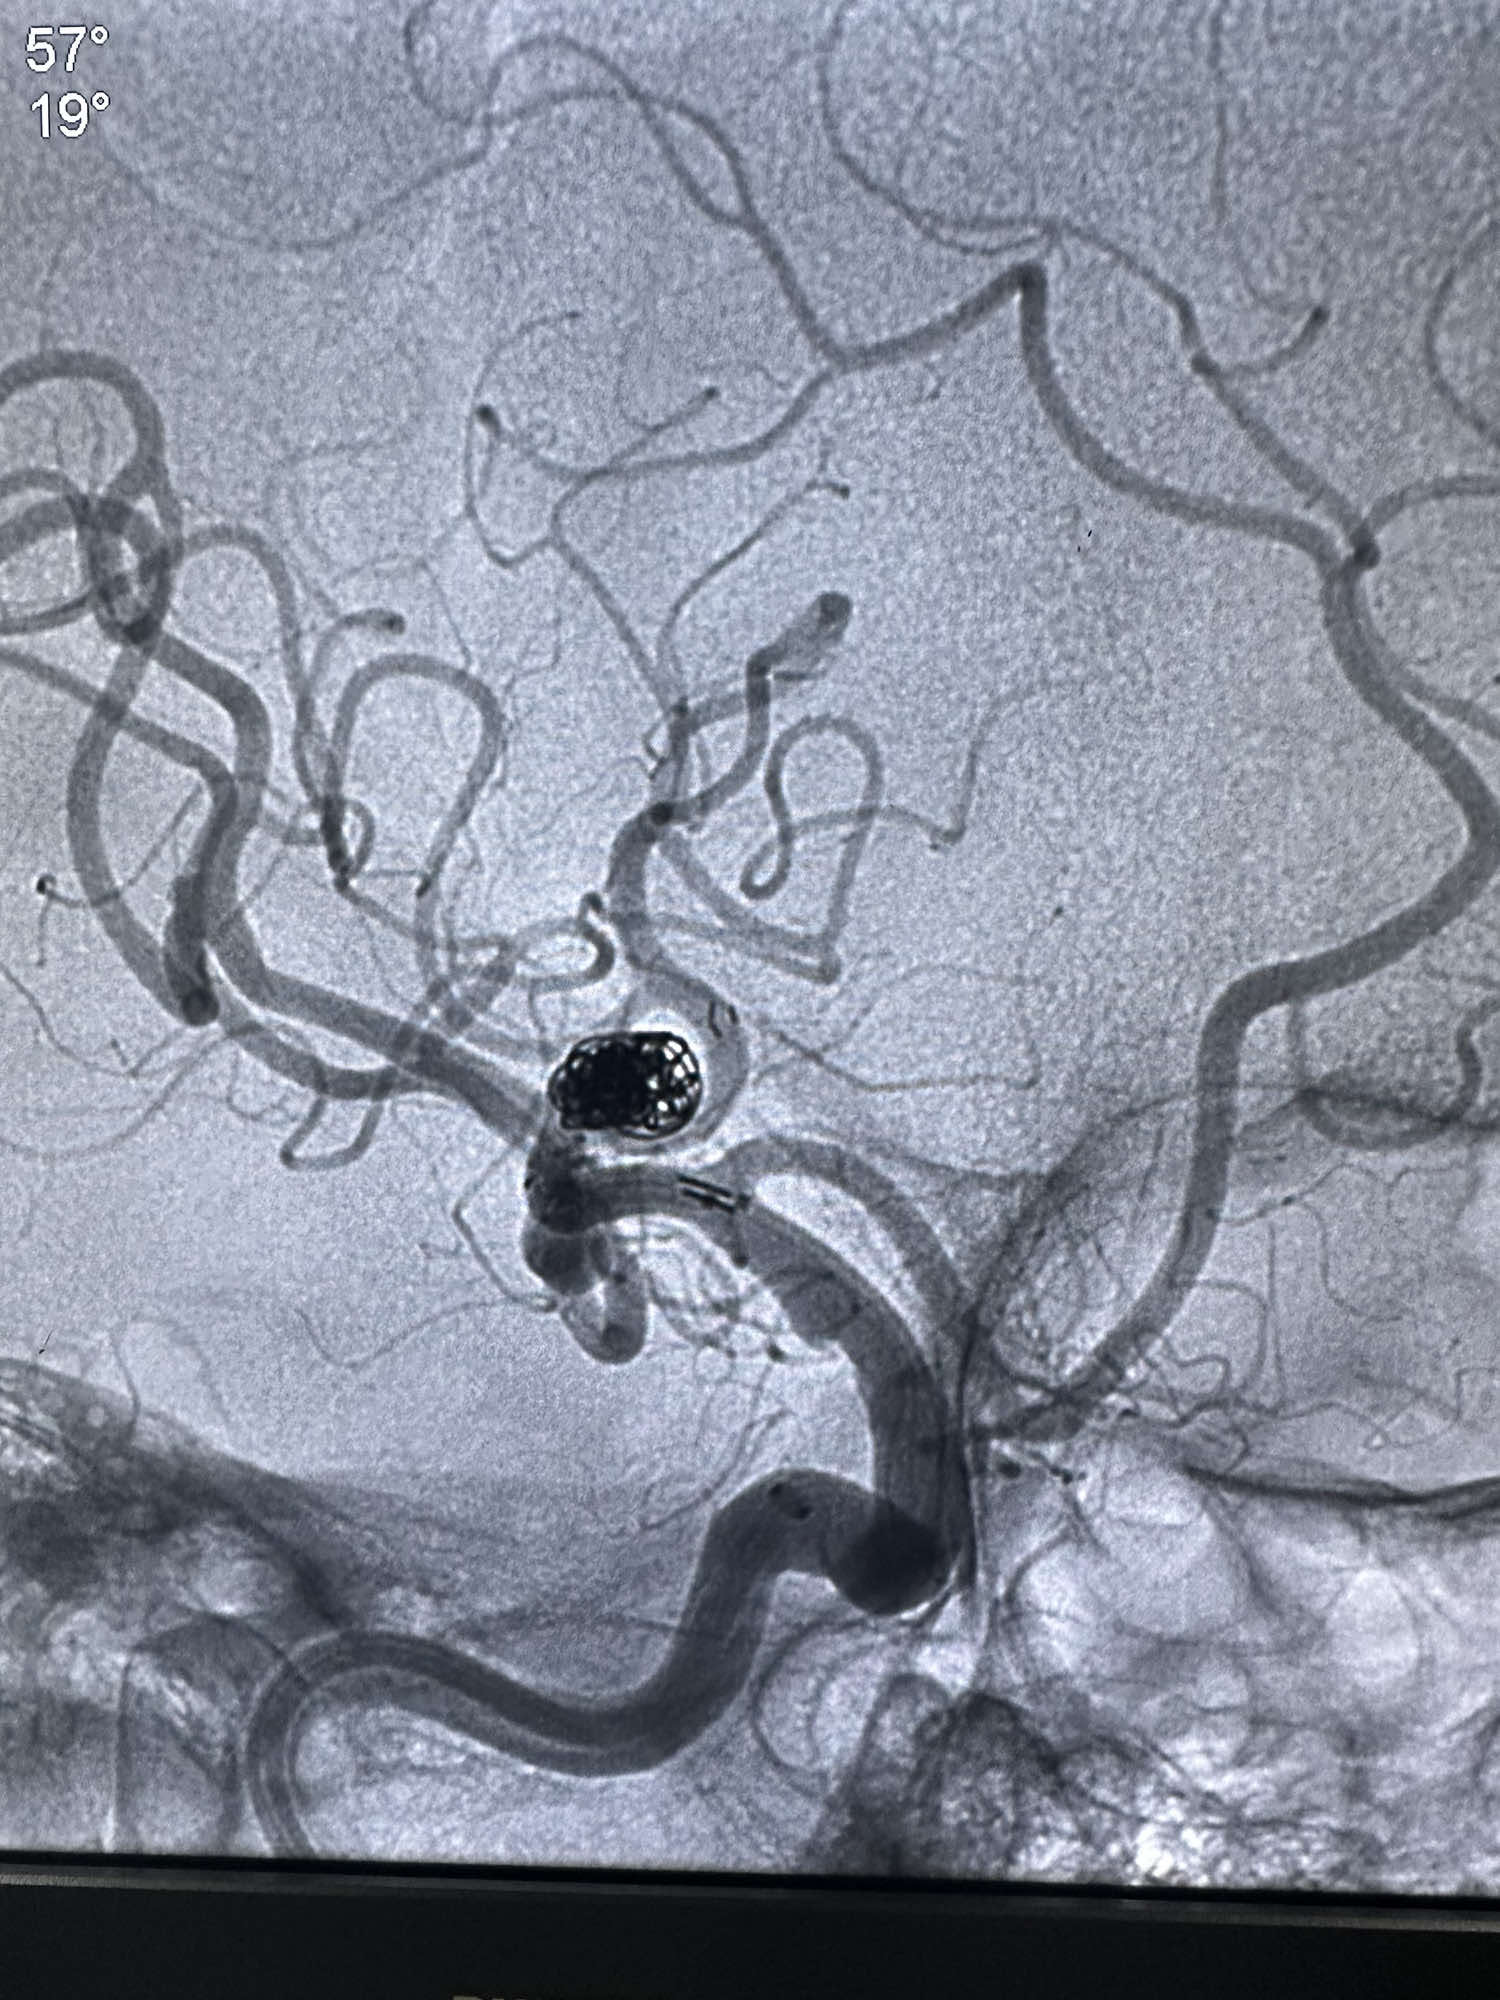

后续填入多枚史赛克的弹簧圈

最后圈的形态